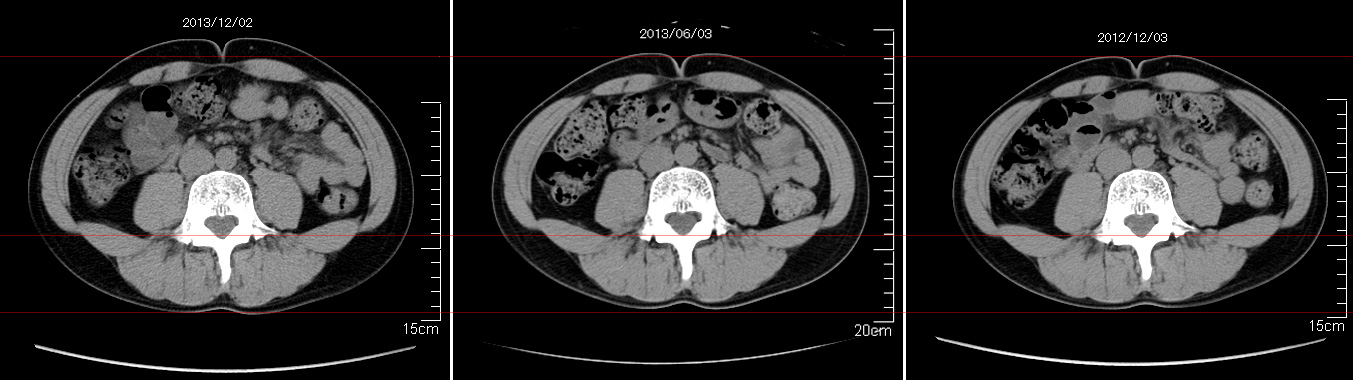

マーカー、CT画像、問題なし!!

通常の血液検査結果も文句なしの正常値がズラ~っと並んだ!!

間違いなくヨメの食事のおかげである。ほんとうに感謝である!!

ちなみに最近少々腰周りの肉付きが気になっていたのだが・・・。

左から2013年12月、2013年06月、2012年12月と背骨の位置は合わせて並べてみた。

6月まではあまり変化がなかったが、この半年で明らかに違う。

背中側の脂肪がやや増えてはいる。

でも最も大きな違いは、腸なのか、やたらと内臓が膨れている・・・。

一言で言うと食べすぎ?!?!

食事は野菜中心ではあるが、確かによく食べているw。

せっかくスーツのウエストを詰めたんだからこれ以上にならないようにしたい。

半年に一回の定期検査である。

6月より太ったからCT画像の腹脂肪が気になる・・・。